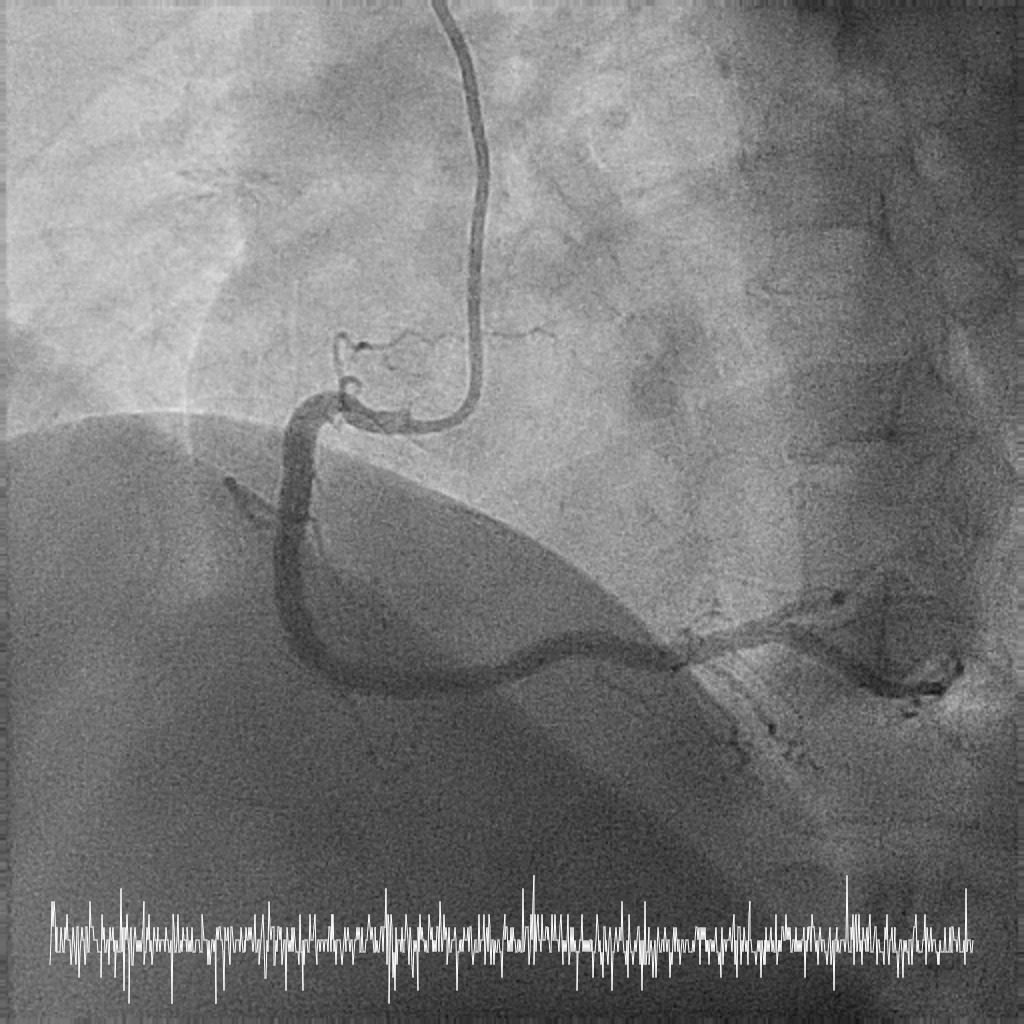

Relevant Catheterization Findings

Coronary angiography performed via right radial approach with a 5F Optitorque diagnostic catheter.

LMS: Ostia LMS 99% stenosis with pressure dampingLAD: Proximal LAD 30-40% stenosisLCx: NormalRCA: Dominant. Normal.

Patient developed short run VT during engagement to left main.

She was referred for coronary artery bypass graft however the patient strongly refused, hence the decision for CHIP-PCI to an unprotected, severely stenotic left main artery.

LMS: Ostia LMS 99% stenosis with pressure dampingLAD: Proximal LAD 30-40% stenosisLCx: NormalRCA: Dominant. Normal.

Patient developed short run VT during engagement to left main.

She was referred for coronary artery bypass graft however the patient strongly refused, hence the decision for CHIP-PCI to an unprotected, severely stenotic left main artery.

Femoral approach was chosen with a 7F sheath. A 7F JL4 guiding catheter was used for better support. JL4 was not coaxially engaged but positioned close to the ostial LM. Sion Blue ES was wired into LAD from the aortic cusp. A BMW wire was wired into LCx to provide additional support and as a safety wire in case of plaque shift into ostial LCx. Ostial LM was predilated with 3.0/10mm NC balloon at 12ATM which was delivered via Sion Blue ES with the guide and wire floating in the aorta. IVUS after predilatation revealed an ostial LM MLA 5.28mm2 with vessel size 4.0mm. Proximal LAD measured 3.0mm in size and exhibited fibrotic plaque with 70% plaque burden. Both ostial LM and proximal LAD were predilated with 3.0/15mm NC balloon delivered using the floating guide and Sion Blue ES. A 3.0/33mm DES was delivered and deployed with similar technique into proximal LAD using multiple projections for precise positioning to ensure proximal stent edge protrusion of 1-2mm into the aorta. POT of LM and ostial flare were performed using 3.75/15mm NC balloon. Proximal LAD was postdilated with 3.0/15mm NC balloon. IVUS confirmed a well-opposed stent without stent edge dissection. The final ostial LM MSA was 9.7mm2, with stent protrusion (1.7mm) into the aorta (less than one quadrant). The entire ostial LM was covered with stent struts.